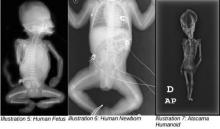

Cлева направо - человеческий зародыш, новорождённый, атакамский гуманоид.

Мумифицированный гуманоид, о котором идёт речь, имеет длину всего 6 дюймов. До последнего времени не было известно подробной информации об обстоятельствах при которых была сделана находка, однако в 2013 году часть сведений раскрыл репортёр Антонио Хунеус. Первое упоминание об обнаружении мумии странного существа появилось в местной чилийской газете. Там рассказывалось, что мумия была обнаружена вблизи города Ла Нориа в заброшенной церкви и была завёрнута в белую ткань. Отмечались отличия от человеческой анатомии – наличие девяти пар рёбер и необычная форма черепа.

Несмотря на то, что незадолго до выхода фильма "Сириус" его создатели заявляли, что ДНК этого существа не может быть классифицирована медиками, в самой ленте появляется учёный, который сообщает, что "гуманоид" имеет земное происхождение. "Я с абсолютной уверенностью могу сказать, что это не обезьяна. Это человек – ближе к человеку, чем шимпанзе. Он дожил до возраста шести-восьми лет. Разумеется, он дышал, ел, у него происходил обмен веществ. Остаётся под вопросом, каких размеров он мог быть при рождении" – рассказывает Гарри Нолан, представитель Медицинской школы при Стенфордском университете в Калифорнии. Именно он выполнял исследование ДНК мумии. Также учёный сообщает, что его целью было доказать, со всей возможной научной точностью, что речь идёт именно о необычной мутации, а не о внеземной жизни.

Изучение ДНК мумии позволило получить и другие, более подробные сведения о её происхождении. Гарри Нолан считает, что это представитель аборигенного индейского населения, ребёнок мужского пола, который умер в прошлом веке. Тем не менее, он признаёт, что не все биологические особенности мумии получили объяснение, и планирует в скором времени опубликовать результаты своих исследований.